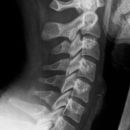

Halswirbelsäule lateral

Indikation

Fraktur, Schleudertrauma und degenerative Veränderungen

Lagerung

aufrecht sitzend am Stativ

Arme seitlich hängend, aktiv nach unten ziehen lassen

Kopf gerade und Kinn leicht angehoben

Zentralstrahl

ZS senkrecht auf Objekt- und Detektormitte

Quer: 2 QF unter Kieferwinkel

Längs: ca. Processus mastoideus

Tiefenblende anpassen

Einblendung

oberes Licht Tragus, lateral Prominens im Licht

Qualitätskriterien

Alle 7 HWK lateral dargestellt, orthogonale Darstellung der Grund- und Deckplatten, Processus spinosus des 7. HWK vollständig dargestellt, Mandibula überdeckt HWS nicht.